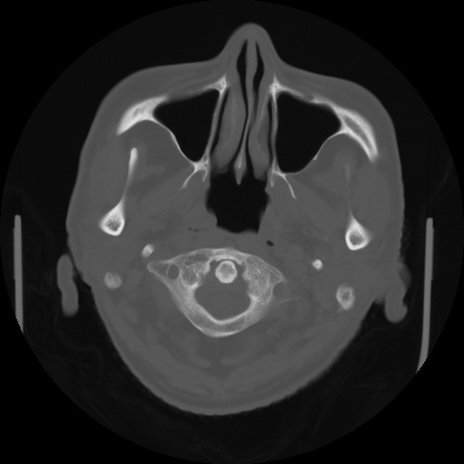

【頭部】症例5 CT(横断像)

【症例】80歳代 男性

【主訴】頭部打撲

【現病歴】外出先で椅子から立ち上がる際に、つまづいて後方へ転倒し受傷。転倒時に意識はあった。

【既往歴】高血圧、不整脈、アルツハイマー病

【身体所見】BP 217/71、HR 96、JCS1-1、 難聴あり、顔色良好、右後頭部に擦過創あり。神経学的異常なし。

症例5の画像所見と診断は?